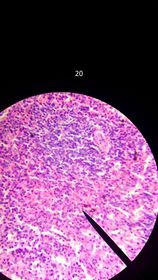

Eosinofilos, neutrofilos, eritrocitos